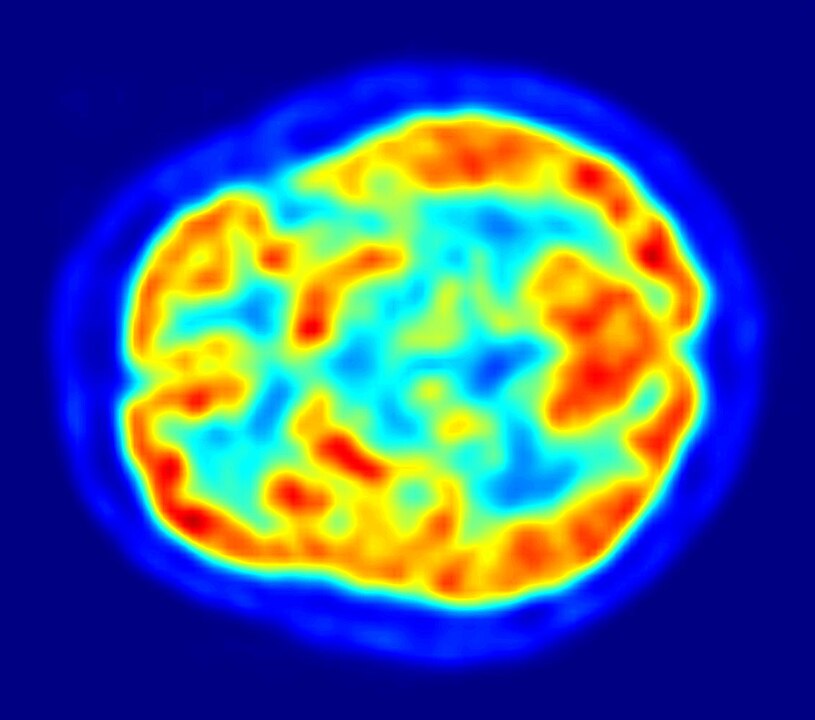

Negli anni ’50 e ‘60 del novecento, i fisici iniziarono quindi a esplorare l’uso dei positroni nella diagnostica per immagini, e nacque la Tomografia a Emissione di Positroni (PET). Questa tecnologia sfrutta i positroni predetti da Dirac per creare immagini dettagliate del funzionamento interno del corpo umano, permettendo ai medici di vedere oltre la struttura dei tessuti e di osservare direttamente i processi metabolici in atto.

Funziona così: si inietta una specifica sostanza radioattiva nel corpo del paziente, spesso legata a molecole come il glucosio. Le cellule tumorali, per esempio, hanno un metabolismo molto attivo e tendono ad accumulare una maggiore quantità di glucosio rispetto alle cellule normali. La sostanza radioattiva scelta, decadendo spontaneamente, emette positroni. Appena questi incontrano gli elettroni del tessuto circostante, quindi dopo un viaggio brevissimo di pochi millimetri, si annichilano. Emettono quindi due fotoni gamma, ovvero ad energia ancora più alta dei raggi X, e viaggiano in direzioni opposte. I rilevatori posti intorno al corpo del paziente captano questi fotoni e, utilizzando sofisticati algoritmi, creano immagini dettagliate che mostrano dove il tracciante radioattivo si è accumulato. Scoprendo quindi dove si accumula maggiormente il glucosio, si può rilevare la presenza di tumori, infiammazioni o altre anomalie del metabolismo.

Questa tecnologia ha rivoluzionato la diagnosi e il trattamento del cancro, permettendo ai medici di identificare tumori in stadi molto precoci, monitorare la risposta ai trattamenti, e pianificare interventi chirurgici con precisione millimetrica.